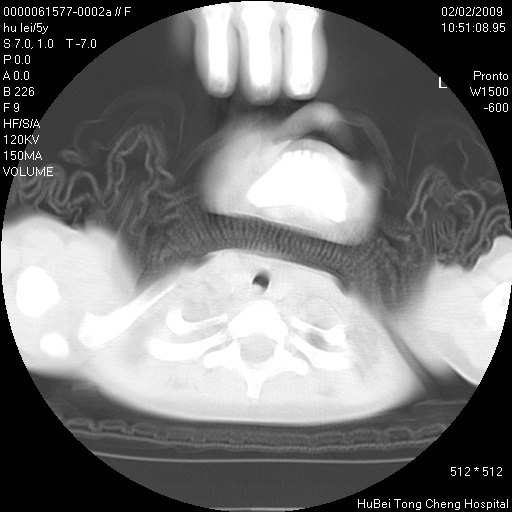

标题: PED1732:M5Y,右肺囊性占位!

患者:男,5。无明显不适,拍胸片考虑右肺囊肿。

行ct扫描,图象如下:

右肺巨大囊肿或包虫

考虑先天性巨大支气管肺囊肿,建议包虫实验除外肺包虫。

右肺巨大囊性占位性病变;考虑巨大肺囊肿,不排除淋巴管瘤可能。

病灶与前胸壁和右上纵隔、叶间裂界限不清,病灶前缘及内侧缘看不到正常的肺组织,不能排除包裹性积液。